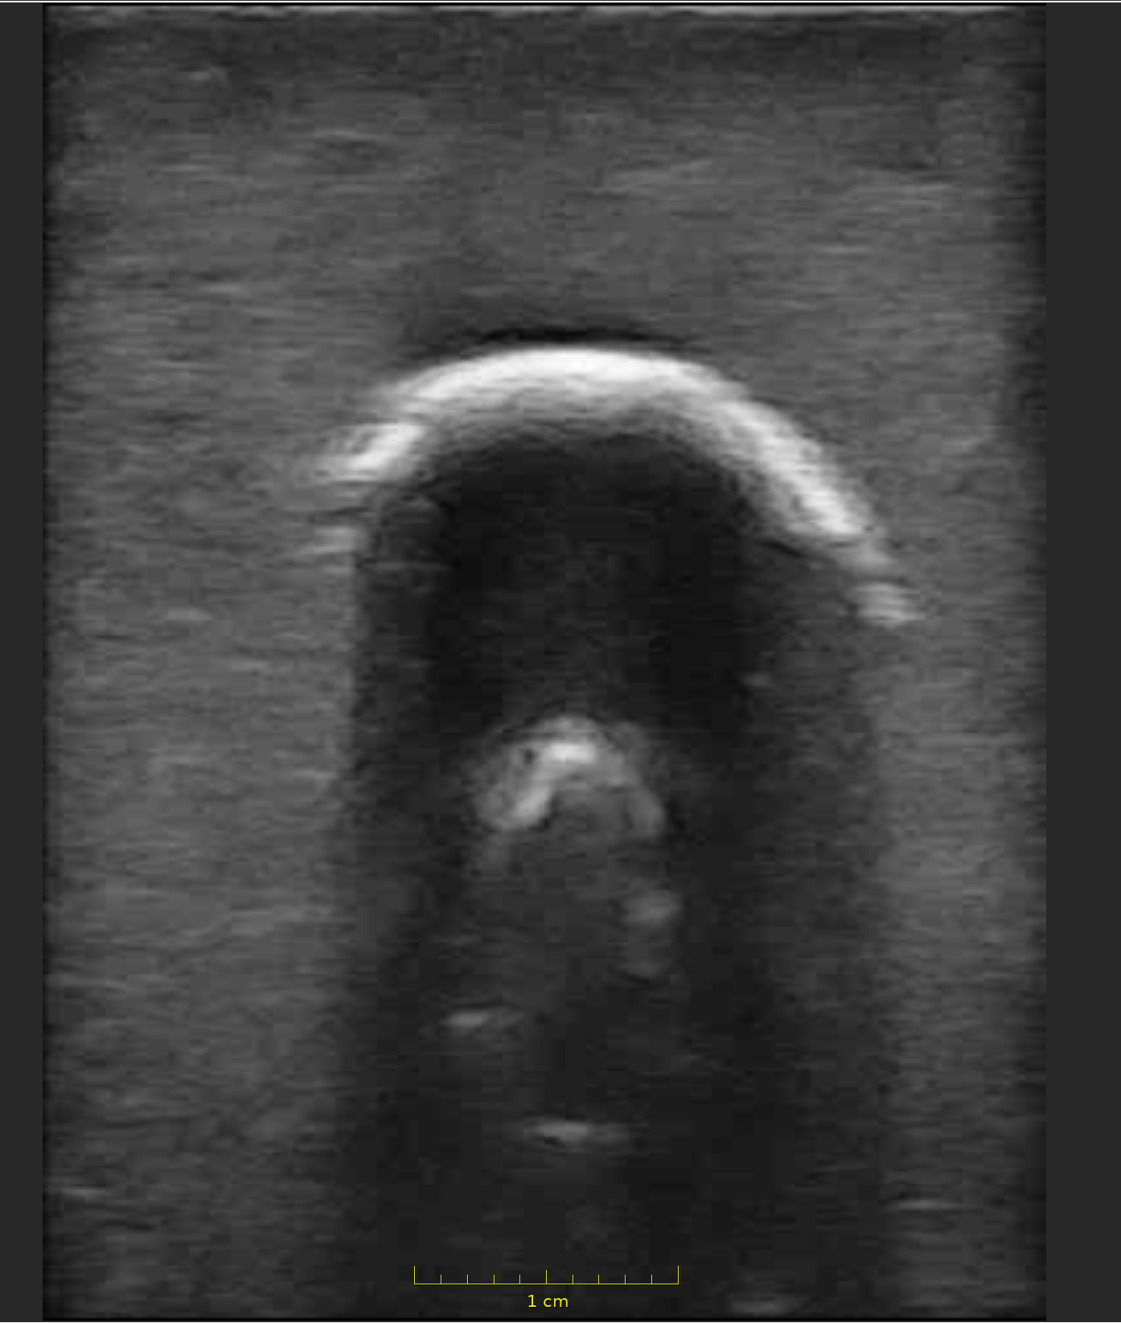

Wir fertigen Phantome für chirurgische Testoperationen / Lehroperationen und zur Validierung von Ultraschallsoftware. Hierbei fokussieren wir uns auf eine Darstellung der Weichtele und der zugehörigen knöchernen Anatomien. Die verwendeten Materialen stellen die Anatomie nicht nur optisch realitätsnah dar, sondern sind auch bezüglich der Haptik, sowie der Bearbeitung (Schneiden, Sägen, Bohren) der Realität nachempfunden. Mit unseren Phantomen können Sie sowohl Schulungsoperationen als auch Testungen von neuartigen Implantaten durchführen und die Ergebnisse mittels Bildgebung kontrollieren.

Bereits realisierte Phantome